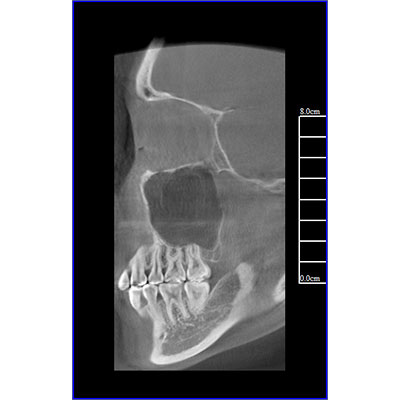

專有三維重建算法,可提供任意位置高清斷層影像。

可同時觀察軸向面、冠狀面和矢狀面圖像,方便臨床診斷。